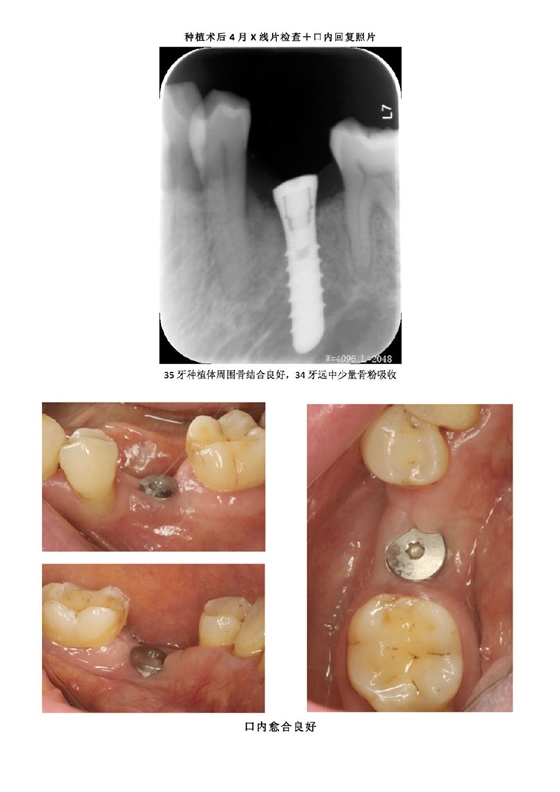

首頁牙周防治 牙周病患者種植治療+鄰牙GTR病例匯報(bào)

牙周病患者種植治療+鄰牙GTR病例匯報(bào)